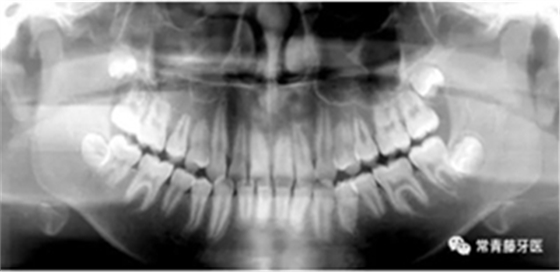

(1)直絲弓矯治器排齊上牙列,配合活動腭桿擴大上牙弓;

(2)上頜顴牙槽嵴植入種植釘,壓低上后牙,糾正開頜;

(3)拔除38、48,在下頜6、7間植入種植釘,整體遠(yuǎn)移下牙列。

6個月,上牙列擁擠得到解除。上下頜植入種植釘,用于上后牙壓低及下牙列遠(yuǎn)移。

14個月,前牙開頜得到改善,配合使用垂直牽引。

16個月,前牙開頜糾正。